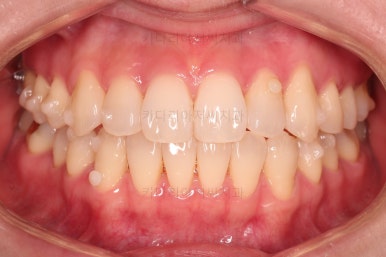

1. 초진

초진 시 입안의 모습입니다.

덧니가 눈에 띄고요.

맞물림이 긴밀하지 못한 상태였습니다.

전반적으로 약간 삐뚤지만 많이 심하다고 보긴 힘들었습니다.